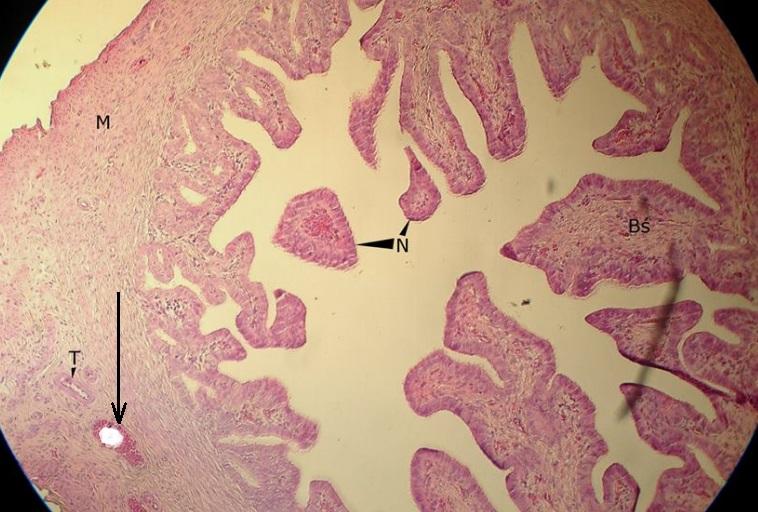

Pytanie 670

tętnica (jajowód)

Pytanie 671

Pytanie 672

żyła (jajowód)